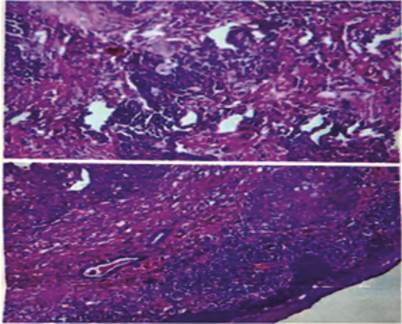

A 70 year old female patient presented to outpatient department of Sri Siddartha Medical College, Tumkur with history of lower lid swelling in RE since 4 months which began slowly, progressed, and was first painless She thereafter experienced slight pain for the last one week. No history of other comorbidities like diabetis mellitus, hypertension, no previous surgical history. On ocular examination: Best corrected visual acuity- RE 6/36 LE 6/18 .On slit lamp examination oval shaped lobulated swelling with multiple yellowish pinpointed out pouching with ulcerated conjunctival side measuring about 6×4 mm prolapsed out of medial conjunctival sac [Figure 1&2]. On Palpation there was no tenderness, mass was mobile & no excoriation was present. Transillumination test was negative. Punctual & sac patency assessed with 00-0 bowmen's lacrimal probe and syringing. No palpable submental and submandibular lymphnodes. In both eyes, an anterior segment examination revealed immature senile cataract. The rest of the anterior and posterior segments of both eyes were within normal limits.On impression cytology it was non conclusive squamous cell neoplasia (RE). Local excision of mass done with bowmens probe in-situ and excised mass has been sent for biposy [Figure 3]. The mass's histopathology revealed meibomian gland cancer with pagetoid dissemination. [Figure 4]

Figure 4: Histopathology of the lesion (low power 10x) which shows meibomian gland carcinoma with pagetoid spread